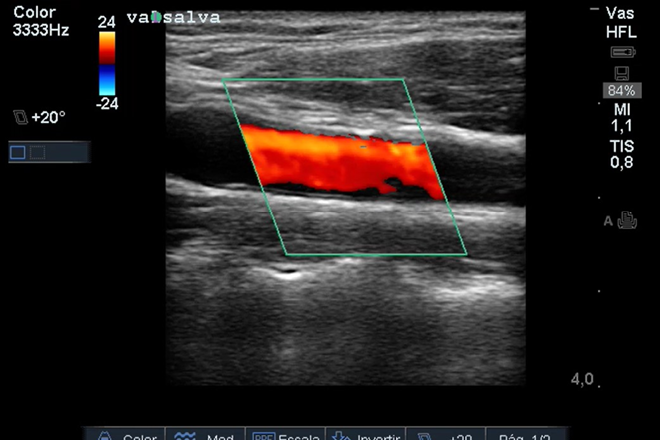

El propósito de este estudio es evaluar, a través de ultrasonografía (US), el espesor medio intimal (EMI) como marcador de riesgo cardiovascular (RCV) temprano en pacientes diagnosticados con Hipercolesterolemia Familiar (HCF), Diabetes tipo 1 (DBT_1) y obesidad (OB), en comparación con un grupo control.

Varios estudios han confirmado que la ecografía es un indicador válido de la progresión de la enfermedad arteriosclerótica en adultos, y hay evidencia de que esta progresión comienza desde la niñez. Existe una fuerte asociación entre niveles elevados de LDL en adultos jóvenes y el riesgo subsiguiente de enfermedad arterial coronaria.

En este estudio participaron 107 pacientes: 24 con HCF, 40 con DBT1 y 43 con OB, junto con un grupo de control de 14 niños y adolescentes. Se les realizó una ecografía de los vasos del cuello, lo que reveló que los tres grupos de pacientes con enfermedades crónicas y riesgo cardiovascular aumentado en la edad adulta presentaban alteraciones tempranas en el espesor medio intimal de las arterias carótidas durante la etapa pediátrica, con resultados estadísticamente significativos.